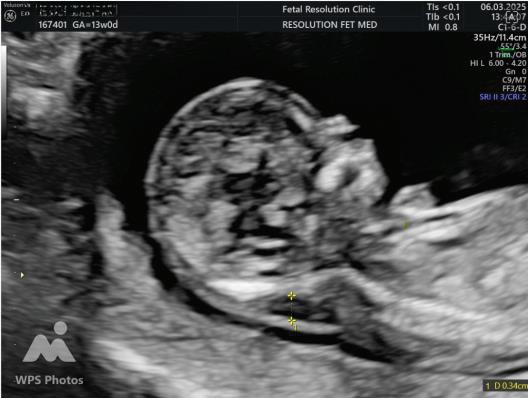

NASAL BONE:

Hypoplasia defined as length <2.5mm.

Absent METHOD OF MEASUREMENT

• Mid saggital plane.

• Good face profile.

• At 45 degree angle with imaginary line from forehead to chin.

• 3 echogenic lines.

• Absent nasal bone is more common if The gestation is 11 than 13 weeks. The fetal nuchal translucency is high. The mother is Black.